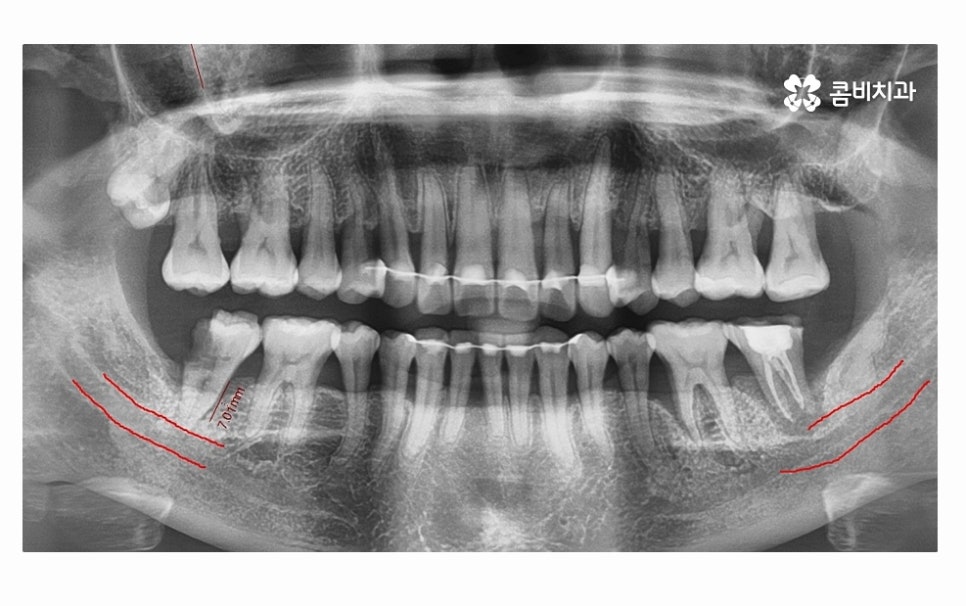

치아를 단단하게 고정해야 하는 잇몸 뼈가 치주염으로 인해

파괴되면 치아를 잃게 될 수 있는데 더 큰 문제는

잇몸에 발생한 염증이 주변 잇몸이나 턱뼈까지 손상을

줄 수 있다는 점이며 잇몸질환의 경우 초기에는

잇몸질환이 치아의 뿌리 염증까지 이어져서 어금니 발치까지

이어진 사례의 경우에는 발치 후 잇몸질환의 회복과

잇몸 뼈가 건강하게 차오르도록 각별한 주의를 기울여야 하며

필요한 경우에는 뼈이식을 진행해야 할 수 있어요.